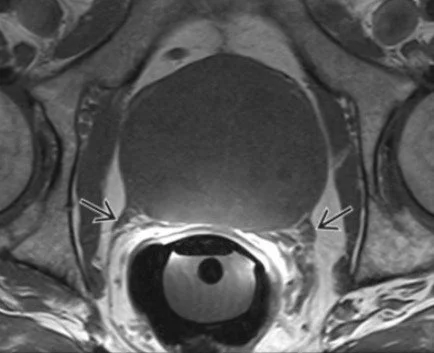

Neurovascular bundle

• The straight lines that look like they are extending laterally from the posterior border of the prostate

• If they look hazy then consider involvement, doesn’t look like definitive invasion can just have haziness around it

• Black arrows in image below